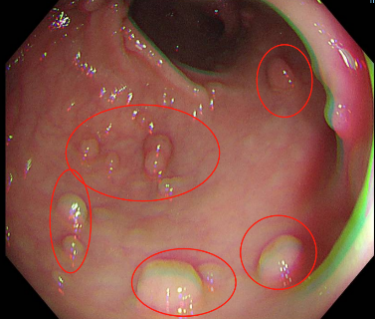

在肠镜检查时,医生看着屏幕,觉得“眼花缭乱”,密密麻麻的肠息肉有数百枚!

随后的病理结果提示,小秦确诊结直肠多发息肉病,其中多枚较大息肉已经进展为腺癌,且CT显示肝脏有异常结节,考虑癌细胞转移,已经到了晚期,仅切除肠道病变对生存意义不大。目前小秦在我院肿瘤科进行化疗,希望能将肿瘤缩小转化,创造手术机会。医护对此都感到很痛心。

(肠息肉—癌前病变—肿瘤)